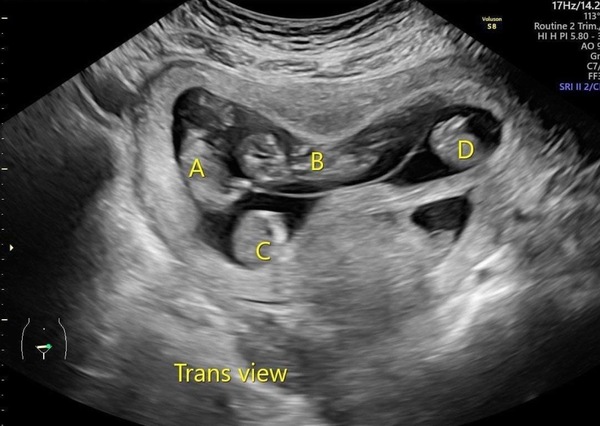

▲郭小姐接受RFA減胎手術前的同卵四胞胎(A、B、C、D)超音波影像。(圖/蕭勝文醫師提供)

蕭勝文主任說明,郭小姐試管一開始植入兩個胚胎,其中一個胚胎發育為罕見的同卵四胞胎,發生率約6000萬分之1,另一個胚胎則自行萎縮。當時,她與家人尋求協助幾乎都是建議直接放棄四寶,轉診至台北長庚已懷孕第11週,超音波下看到4個有心跳的孩子,確認是同卵四胞胎。

由於四胞胎發生早產與母體併發症的風險太高,因此蕭勝文主任也建議他們減胎,經超音波精準定位再以射頻燒灼(RFA)阻斷胎兒的血流供給,進而達成減胎目的,這也是目前的國際趨勢。